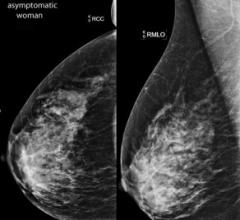

Despite decades of progress in breast imaging, one challenge continues to test even the most skilled radiologists ...

According to the European CanCer Organisation (ECCO), there are more than 1.6 million new cases of breast cancer diagnosed globally each year. This number has been increasing at a rate of 3.1 percent per year. As Prof. Peter Boyle, director of the University of Strathclyde Institute of Global Public Health at the International Prevention Research Institute (iPRI) in Lyon, France, told conference-goers at the European Breast Cancer Conference (EBCC-9), “We need to make a reduction in the number of women developing and dying from breast cancer a global priority.”